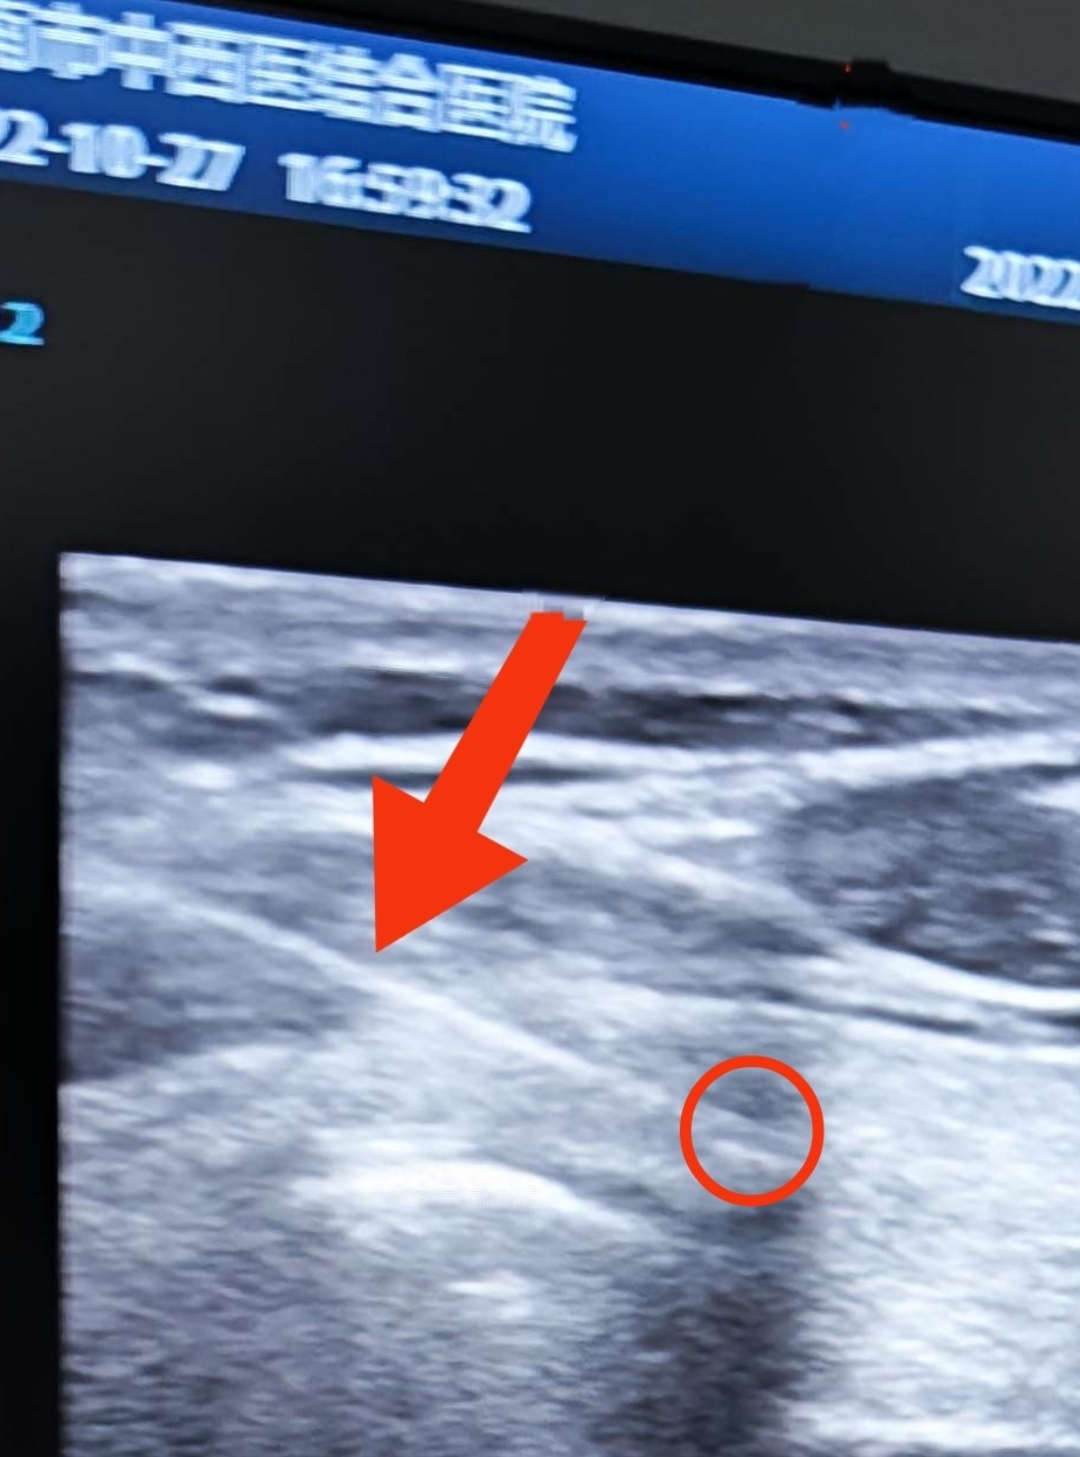

上(shàng)周五,門診一(yī)名女(nǚ)性患者來(lái)診,查體(tǐ)彩超發現(xiàn)甲狀腺結節

如(rú)下(xià)圖

穿刺圖像

放(fàng)大圖像